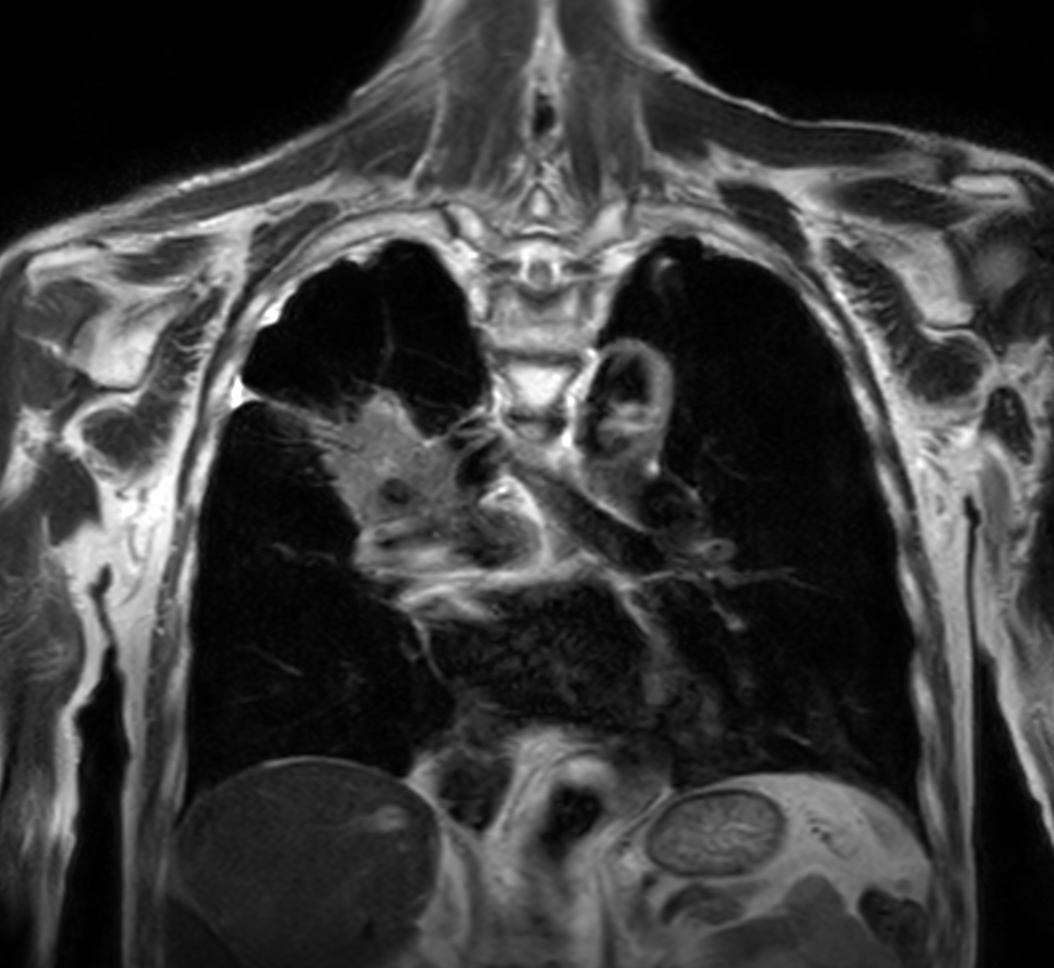

Patient with lung cancer. The ExamCard includes techniques for efficient fat-free imaging over large field-of-views (mDIXON XD), a diffusion procedure with less distortion (DWI TSE XD), a multi-phase contrast-enhanced sequence (4D FreeBreathing) to improve imaging confidence and Compressed SENSE to accelerate the entire exam.

T2w TSE Compressed SENSE